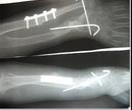

儿童陈旧性孟氏骨折

术后肘关节侧位片

术后1个月肘关节侧位片

儿童陈旧性孟氏骨折,术前桡骨小头陈旧性脱位,经截骨矫形治疗后1个月,桡骨小头已复位,患儿肘关节屈伸功能(1-2图),前臂旋转功能(3-4图)正常